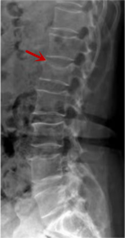

利器一:X線/DR

腰椎X線片作為最基礎(chǔ)的影像檢查手段,利于X線穿透人體組織后成像,以其快捷、直觀、價格低廉的特點,X線檢查主要包括腰椎正側(cè)位、雙斜位以及過伸過屈位。主要用于觀察腰椎骨骼的情況,如椎體是否有骨折、骨質(zhì)增生程度、生理曲度的變化、椎體移位的情況等。然而,X線檢查也有它的局限性,無法判斷是骨折的新舊,對于椎體內(nèi)部結(jié)構(gòu)和周圍肌肉韌帶組織(如脊髓神經(jīng)、椎間盤、韌帶等)的顯示不佳,另外X線作為有輻射檢查,孕婦及嬰幼兒謹(jǐn)慎選擇。

箭頭提示腰1椎骨折

箭頭提示腰3椎體滑脫